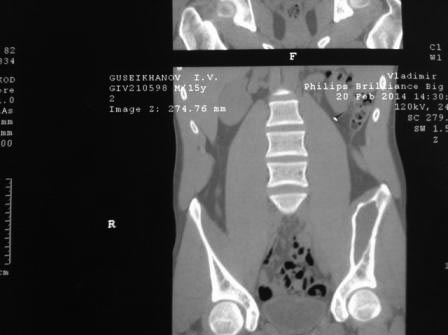

[Ortho] Киста подвздошной кости

Пациент 15 лет, спортсмен, внезапно появились боли в подвздошной области

слева при поворотах и наклонах туловища. В покое ничего не беспокоит.

Пациенту в ЦИТО была выполнена трепан-биопсия образования,

гистологически ничего плохого не выявлено. Хотят оперироваться в

Махачкале. Возникает два вопроса: 1)каким доступом пойти? 2)чем

заполнять? Доступ проще всего сделать наружне-боковой по гребню

подвздошной и дальше трансосально до полости. Полость очень большая,

аутокости слишком много брать, I-Factor и Силориф если брать 60-90 куб

см выходит на 100-200 тысяч, пациент не рентабельный так сказать. Если у

кого был такой случай в практике, просим совета. И еще вопрос: зона не

опорная, нельзя ли заполнить полость костным цементом ? Как при

гемангиоме тела позвонка.